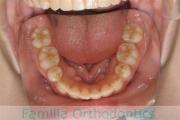

No.23V-061

- 主な症状:

- 叢生

- その他の症状:

- 上下顎前突

- 年齢:

- 23歳

- 性別:

- 女性

- 抜歯部位

- 上:

- 44

- 下:

- 主な使用装置:

- FEA 022

- 治療にかかった費用:

- 88万円

でこぼこを綺麗に並べたいということで来院されました。上下左右から小臼歯を抜歯して、マルチブラケット法を2年半、30回程度通院していただいて行いました。

かなり強い叢生(でこぼこ、凹凸、ガタガタ)のため、保定をしっかりしないと後戻りのリスクが高いケースといえます。

- ≫治療前

-

上顎

下顎